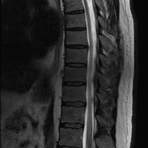

- Abklärung Bandscheibenvorfall

- Beurteilung Einengung des Rückenmarkkanals oder der Neuroforamina im Rahmen der degenerativen Wirbelsäulenerkrankung

- Tumor-/Entzündungsdiagnostik

- Abklärung Spondylolisthesis

- Frakturdiagnostik (Alter und Ausdehnung der Fraktur) z.B. im Rahmen der Osteoporose